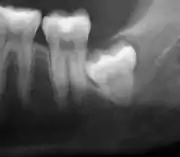

Coronectomy

Coronectomy of impacted wisdom tooth post-op xray showing root remnants (red arrow) and inferior alveolar nerve (green arrow)

Coronectomy is a procedure where the crown of the impacted wisdom tooth is removed, but the roots are intentionally left in place. It is indicated when there is no disease of the dental pulp or infection around the crown of the tooth, and there is a high risk of inferior alveolar nerve injury.[31]

Coronectomy, while lessening the immediate risk to the inferior alveolar nerve function has its own complication rates and can result in repeated surgeries. Between 2.3% and 38.3% of roots loosen during the procedure and need to be removed and up to 4.9% of cases require reoperation due to persistent pain, root exposure or persistent infection. The roots have also been reported to migrate in 13.2% to 85.9% of cases.[31]